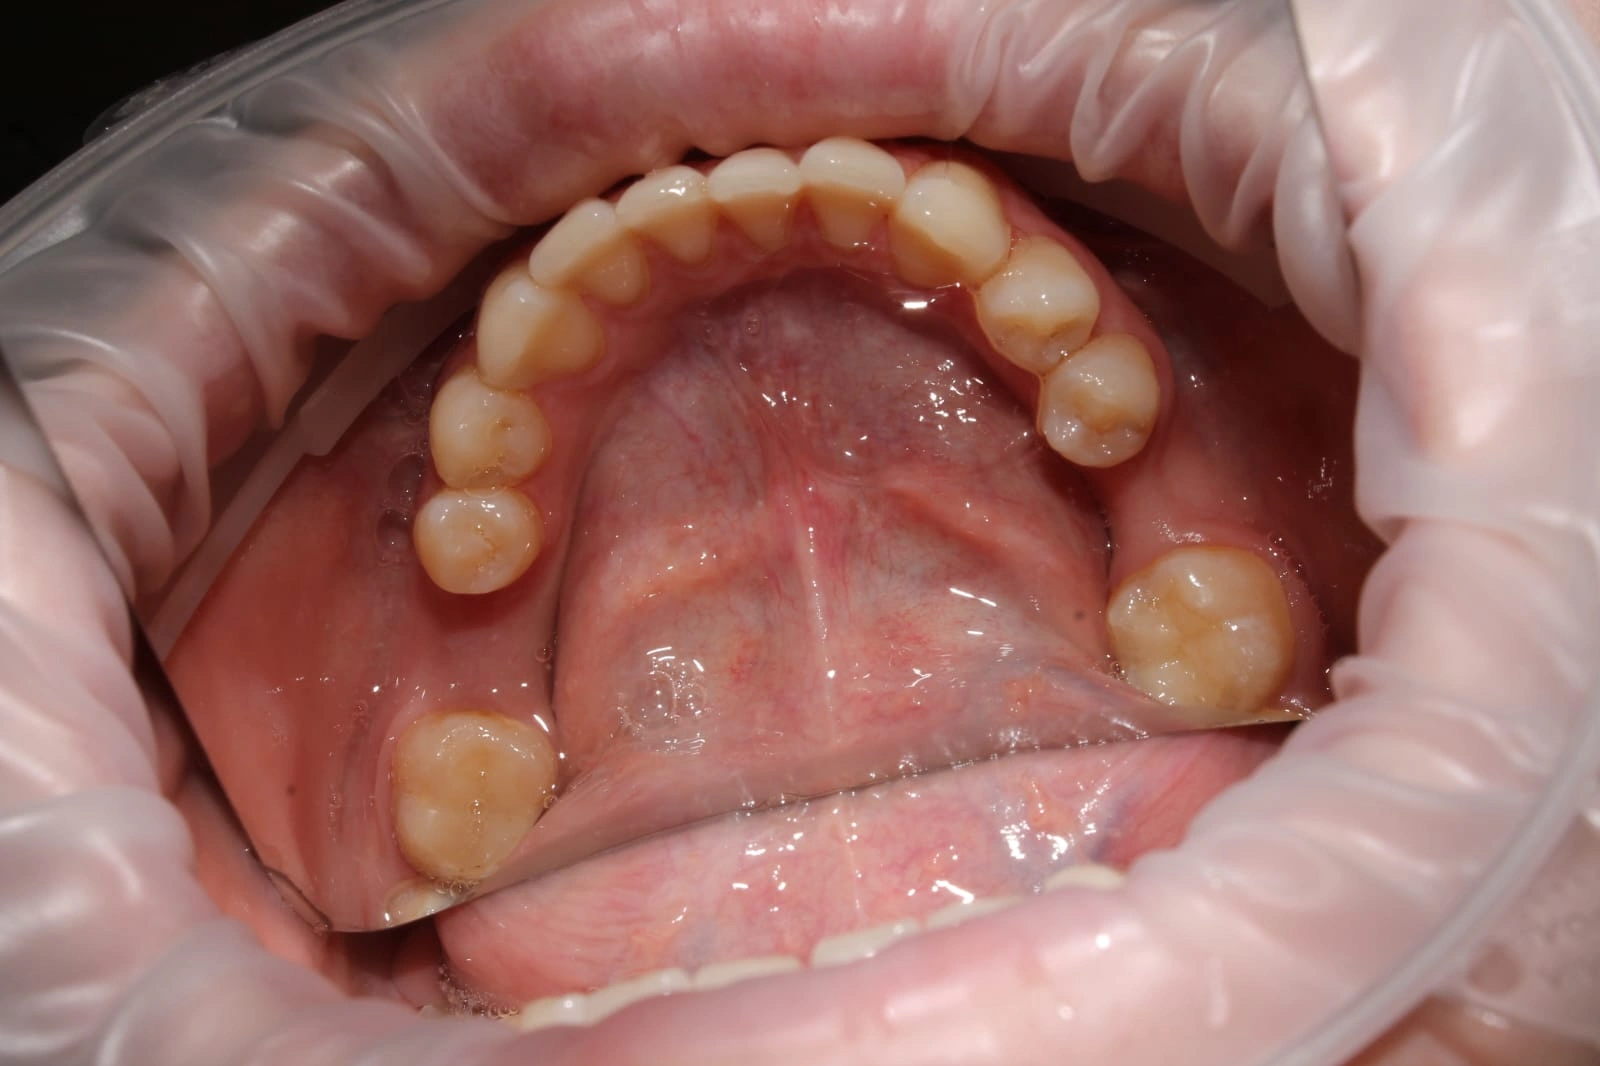

Laser Dentistry is a modern treatment approach that uses focused light energy to perform dental procedures with high precision. This allows dentists to treat tissues gently, with minimal cutting, reduced bleeding, and faster healing all while keeping patient comfort at the centre.

Laser technology also enables more effective bacterial reduction, making it especially useful in treatments like root canal therapy, gum care, and infection management. By targeting problem areas precisely and preserving healthy tissue, Laser Dentistry often reduces the need for more invasive procedures later.